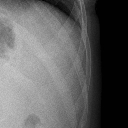

肺挫伤(11.34MB)

肺挫伤

胸腔积液(11.34MB)

胸腔积液